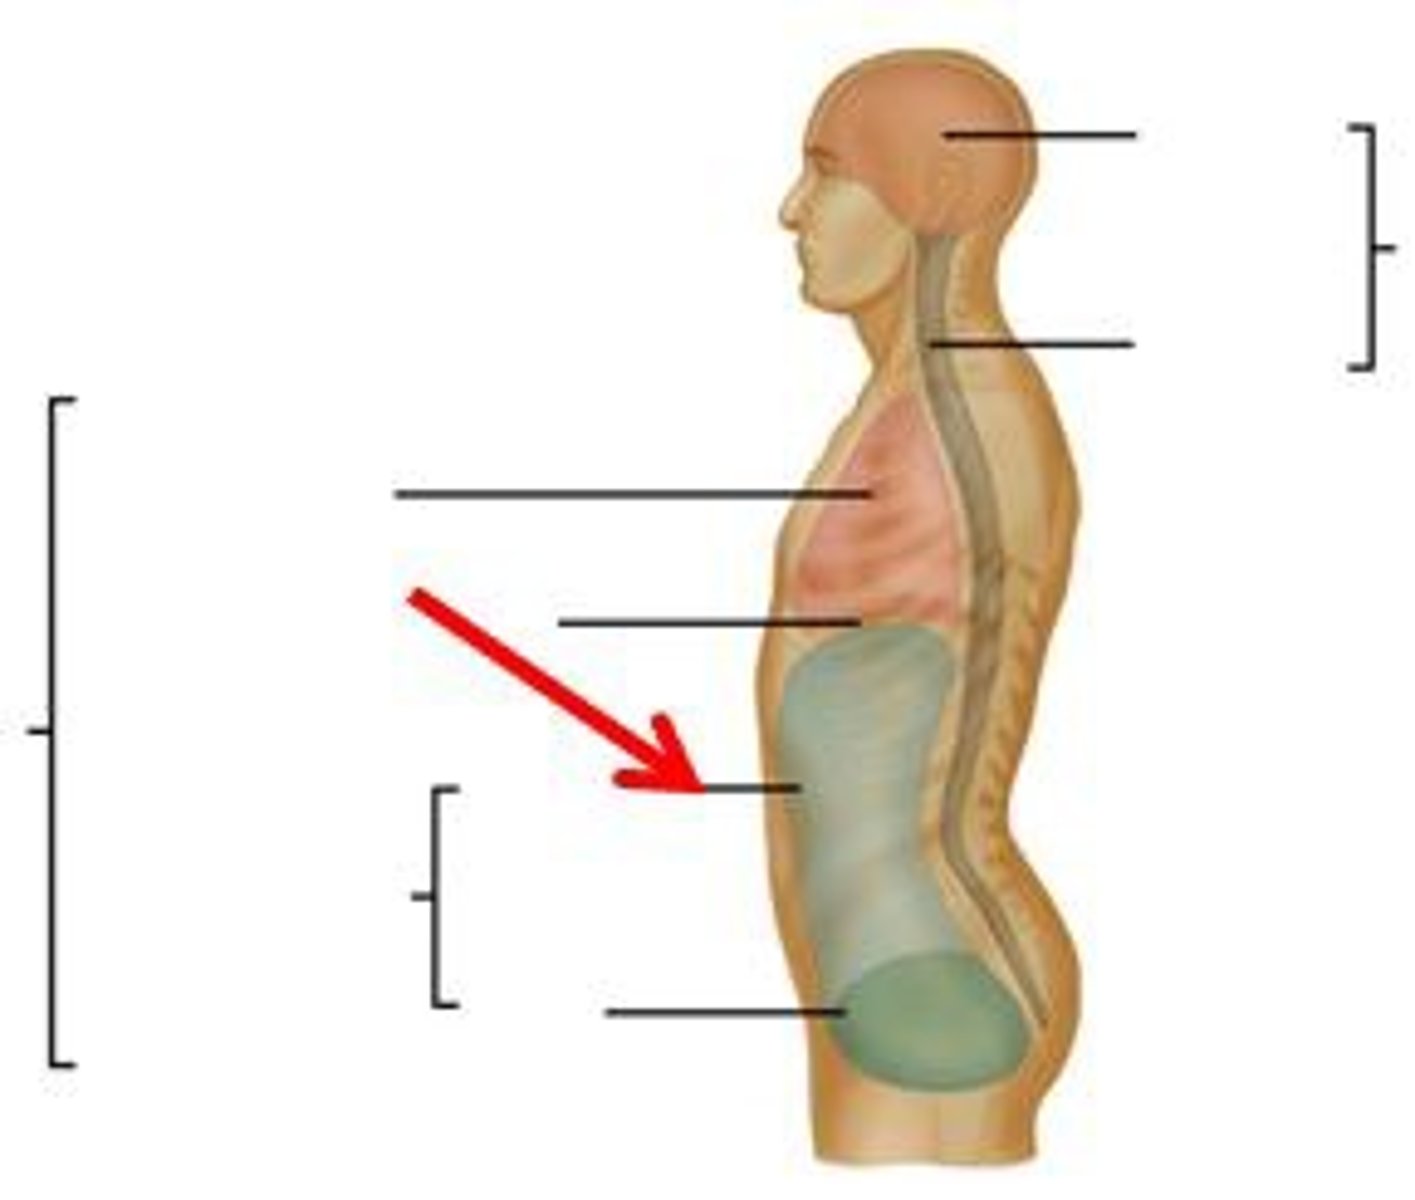

peritoneal cavity

greater sac

peritoneal compartment of the abdominal cavity

lesser sac

peritoneal pouch located behind the lesser omentum and stomach